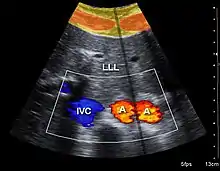

Doppler ultrasonography is used to study blood flow and muscle motion. The different detected speeds are represented in color for ease of interpretation, for example leaky heart valves: the leak shows up as a flash of unique color. Colors may alternatively be used to represent the amplitudes of the received echoes.

Doppler ultrasonography

Doppler ultrasonography employs the Doppler effect to assess whether structures (usually blood)[52][54] are moving towards or away from the probe, and their relative velocity. By calculating the frequency shift of a particular sample volume, flow in an artery or a jet of blood flow over a heart valve, its speed and direction can be determined and visualized, as an example. Color Doppler is the measurement of velocity by color scale. Color Doppler images are generally combined with gray scale (B-mode) images to display duplex ultrasonography images.[55] Uses include:

- Doppler echocardiography is the use of Doppler ultrasonography to examine the heart.[56] An echocardiogram can, within certain limits, produce accurate assessment of the direction of blood flow and the velocity of blood and cardiac tissue at any arbitrary point using the Doppler effect. Velocity measurements allow assessment of cardiac valve areas and function, abnormal communications between the left and right side of the heart, leaking of blood through the valves (valvular regurgitation), and calculation of the cardiac output and E/A ratio[57] (a measure of diastolic dysfunction). Contrast-enhanced ultrasound using gas-filled microbubble contrast media can be used to improve velocity or other flow-related measurements of interest.